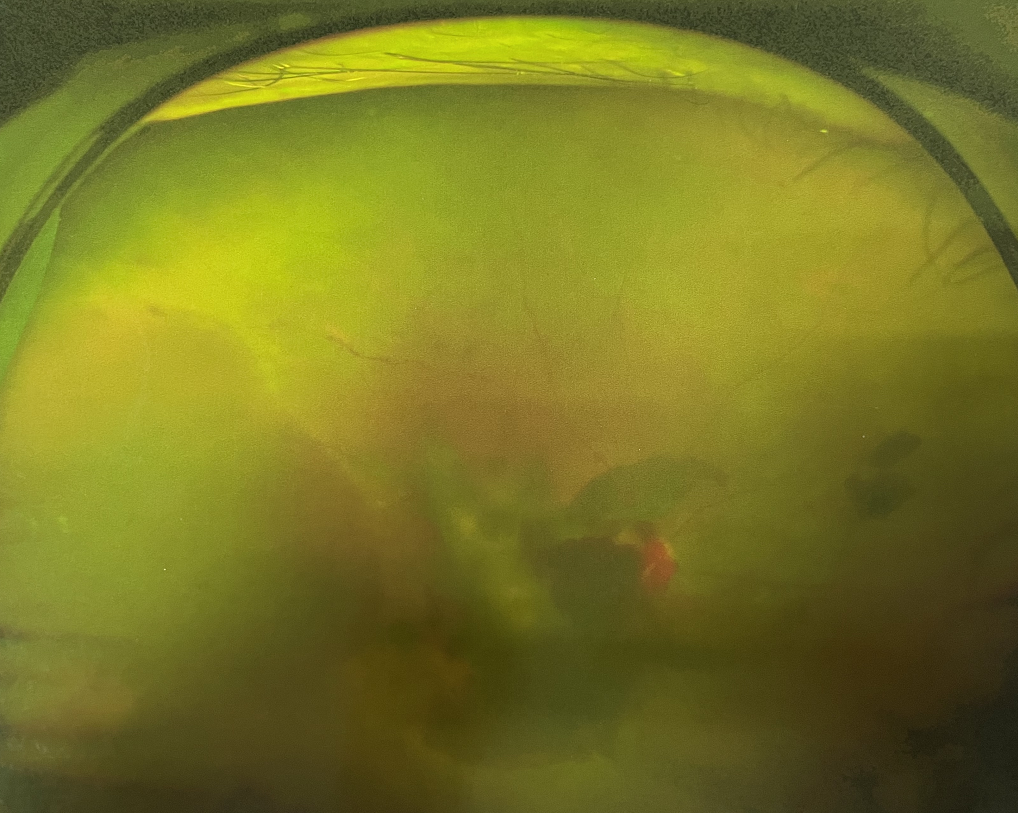

糖尿病視網膜病變是糖尿病在眼部的主要并發(fā)癥,是我國四大致盲眼病之一,主要以視網膜血管改變?yōu)椴±硖卣鳌Q鄣锥啾憩F(xiàn)為視網膜出血、滲出、新生血管及增殖膜形成,嚴重威脅患者的視覺健康。

糖尿病視網膜病變患者早期可能沒有明顯的視力下降,有些患者因為玻璃體出血會出現(xiàn)突然視力下降,晚期患者視力多有明顯下降。

糖尿病視網膜病變可分為六期:

?、衿冢河形⒀芰龌虿⒂行〕鲅c。

?、蚱冢河悬S白色“硬性滲出”或并有出血斑。

?、笃冢河邪咨?ldquo;軟性滲出”或并有出血斑。

?、羝冢貉鄣子行律芑虿⒂胁Aw積血。

Ⅴ期:眼底有新生血管或并有纖維膜增生。

?、銎冢貉鄣子行律芑虿⒂欣w維膜增生,并發(fā)視網膜脫離。